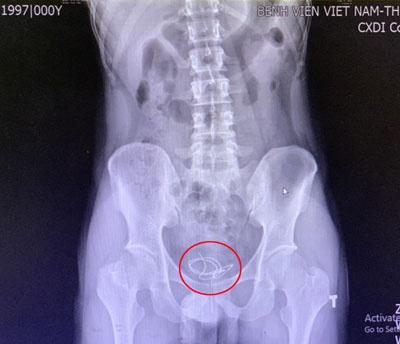

Trước đó, ngày 8/6, thanh niên này đến khám tại khoa Ngoại thận tiết niệu với triệu chứng tiểu khó, tiểu buốt, tiểu rắt. Các bác sĩ đã tiến hành chụp X-quang và phát hiện 1 đoạn dây tai nghe dài khoảng 20cm trong bàng quang của nam thanh niên.

Hình ảnh siêu âm dây tai nghe bên trong bàng quang bệnh nhân